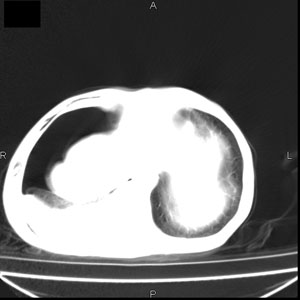

患者男,77岁,于3日前从树上摔下,头部查ct示蛛血,硬膜下出血,上腹部ct未见明显异常,右侧胸腔积液,左侧如常。肺部拍片示右侧肋骨多发骨折住院后今日来查肺部ct,我看到的是1。右侧胸腔血气胸并右肺上叶,中叶压缩性肺不张,2。右肺下叶肺挫伤并多发肋骨骨折,肌内及皮下积气3。左侧少量胸腔积液,我想请教的是3天前左侧胸腔里没有积液今天怎么出现了呢,是什么原因呢?请讨论。

回复楼主   左侧液气胸,液体来源1、肯定有血液成分,多少不一定。2、胸膜腔渗液,由于肺压缩、活动度下降,肯定胸膜吸收有问题,导致积液增多。

因为3天前病人刚摔的时候,左侧胸腔受伤不严重,故而当时没有胸腔积液,但病人受到这么大的伤害,胸膜腔内的液体动态平衡肯定会受到影响,所以过一段时间后才出现胸腔积液。